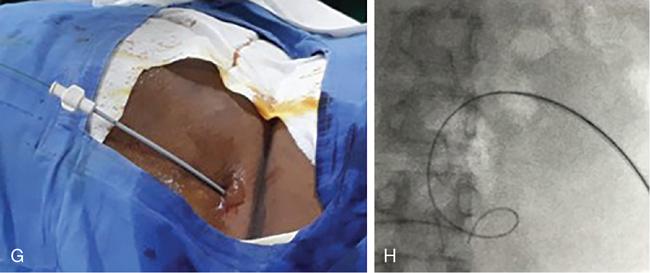

NONVASCULAR RENAL INTERVENTION Amitha Vikrama Nonvascular renal interventions have come a long way and have significantly reduced the surgical mortality and morbidity. It also paves way for short hospital stay and thus reducing the chances of nosocomial infection. They are usually pinhole or keyhole procedures with less distortion of the anatomy and physiology. They vary from image-guided aspiration/biopsy to percutaneous nephrostomy to complex procedures like ureteric stenting, strictureplasty, percutaneous nephrolithotomy etc. Iversen and Brun were the first to perform percutaneous renal biopsy of native kidneys in 1951. Over the years, newer imaging and biopsy techniques have evolved which have increased the biopsy yield to >95% and significantly reduced the complications of renal biopsy, resulting in decreased mortality rates from 0.12% to 0.02% during the last 50 years NOTE: Solitary renal mass lesions suspicious for malignancy should not be subjected to percutaneous biopsy, as there are chances of tumour seeding along the biopsy track. Excision biopsy is preferred for those lesions as it can be curative. USG-guided renal biopsy is the preferred method over blind biopsies. It avoids nontarget biopsies and reduces bleeding risks. Usually the lower pole of the kidneys is preferred site in native renal biopsy. The needle has to be directed into the lower cortex and care taken to avoid renal medulla and collecting system. 18G trucut biopsy needles are usually used in adults. In paediatric population, 20G can be used. Rarely, Coaxial technique is used in very obese patients and in those who are unable to lie prone. It is usually done as an inpatient procedure. Four hours of fasting is required to prevent aspiration of gastric contents during the procedure. Antiplatelets and anticoagulants are stopped at least 3–5 days prior. Informed written consent has to be taken after explaining the risks and benefits of the procedure. Patient is to be positioned in prone and USG-guided marking of the site of biopsy done prior to cleaning and draping. The depth of the renal cortex from the skin surface has to be noted. If the ribs are coming in line with the lower pole cortex, then a cranially angulated path is preferred. After infiltration of 2% lignocaine, the biopsy needle is advanced up to and not into the lower pole cortex. As the kidney keeps moving with respiration, the biopsy should be properly timed to avoid hitting the collecting system and medulla. This method is real-time ultrasound guided renal biopsy (Fig. 10.21.1.1). There is another method practiced in few of the institutes where the location of lower pole of the kidney is marked on the skin after ultrasound screening. The marking corresponds to the lower most renal cortex at the end of normal inspiration and the biopsy path will be perpendicular to the bed without any craniocaudal or mediolateral angulation. The distance between the skin and the renal cortex is measured. The patient will be instructed strictly not to change his position. Then the biopsy will be done blindly without any real time USG guidance. With this method, more number of patients can be biopsied in a short interval time. In a transplanted kidney, which is usually grafted in the iliac fossa, biopsy can be obtained from upper or lower pole. Points to remember: Cortical tangential and cortical non tangential approaches have been described (Fig. 10.21.1.2). Cortical tangential approach is described to have better diagnostic yield with lesser complications. In this approach, the needle track will be almost parallel to the capsule so that only the cortical tissue is targeted (Fig. 10.21.1.3A–C). Renal biopsy can also be done with coaxial technique. In this method, a coaxial needle, one size bigger than the biopsy needle, usually 17G, is inserted up to the renal capsule. The stylet is then removed and the 18G biopsy needle is inserted through the coaxial needle and the required number of biopsy specimens obtained. After this, the rent in the capsule can be sealed off with gelatine plugs before removing the coaxial needle. This helps in preventing bleeding complications. In patients with high risk of bleeding due to coagulation abnormalities, transjugular renal biopsy can be done in which renal vein is cannulated and biopsy done from within (Fig. 10.21.1.3D–F). In obese patients who cannot lie prone, biopsies are done in lateral or oblique lateral positions under CT or USG guidance. CT guidance is especially helpful when the visualization of the kidney is difficult on ultrasound. In these cases, coaxial technique is always helpful. In 2019, KHA-CARI guidelines were first published for renal biopsy. A few of the salient recommendations are given below: It is an image-guided procedure in which the renal pelvicalyceal system is accessed percutaneously which is predominantly used for decompressing an obstructed system and also for various other therapeutic procedures. It is usually done under local anaesthesia and IV sedation. Major procedures might require general anaesthesia. All routine preprocedural blood tests and coagulation profile should be done. Appropriate antibiotics are administered intravenously prior to the procedure. 21G needle, 018 and 035 wires, appropriate dilators, sheath and pigtail drainage catheter. Ultrasound and fluoroscopy is required for guidance. Patient is usually positioned prone on the table. Under special circumstances, lateral or oblique positions are also used. After instillation of local anaesthesia, a 21G needle is used to access the renal calyx under USG guidance. Once the urine flow is seen, nonionic contrast is injected to delineate the renal collecting system. A 018 wire is passed through the needle into the pelvicalyceal system and later exchanged for a 035 wire. Appropriate tissue dilators are used to dilate the track before placing a pigtail drainage catheter. The drain is secured by stay sutures and connected to a urobag. The initial urine sample is to be sent for culture and sensitivity (Figs. 10.21.1.4–10.21.1.6). Ureteric stenting was first described by Zimskind et al endotracheal tube al in 1967. It is one of the commonest procedure done in urology practice It is usually done after doing a percutaneous nephrostomy. The percutaneous nephrostomy (PCN) drain is replaced with a 6F or 8F sheath over a guidewire and ureterogram is obtained to assess the site of stricture or obstruction. Using a catheter and guide wire combination, the stricture is negotiated and the exchange length hydrophilic wire is parked in the bladder. The ureteric length is measured and appropriate-sized double J (DJ) stent is inserted over the wire. Care is taken to get the loops formed at both ends of the DJ stent so that stent migration is prevented (Fig. 10.21.1.7). A variety of delivery systems are available for the deployment of the ureteric stent exist: pusher mechanism, string release and sheath (similar to an inferior vena cava (IVC) filter). Post stent insertion, the nephrostomy drain can be retained for a couple of days. The drain is closed externally and USG screening is done the next day to confirm antegrade flow after which the drain can be removed.